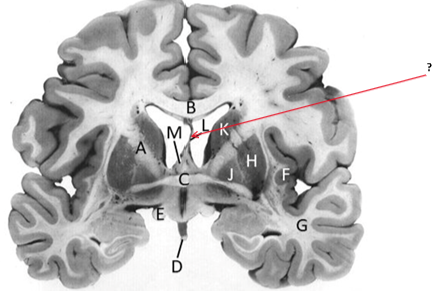

Name this and state its function.

Corpus Callosum.

Putamen.

Name this, state its function, pathways and cellular components.[5 marks]

Caudate nucleus.

Medium spiny neurons utilising GABA and some Cholinergic.

From cortex–>CN–>hippocampus, Gp and thalamus.

Septum pellucidum.

Fornix.

Anterior commissure.

Interconnects:

Infundibular stalk.

Insula.

Name this, state its function, components[2] and the difference in pathways.

Internal capsule.

Anterior limb:

Posterior limb:

Corticospinal tracts and corticopontine tracts: